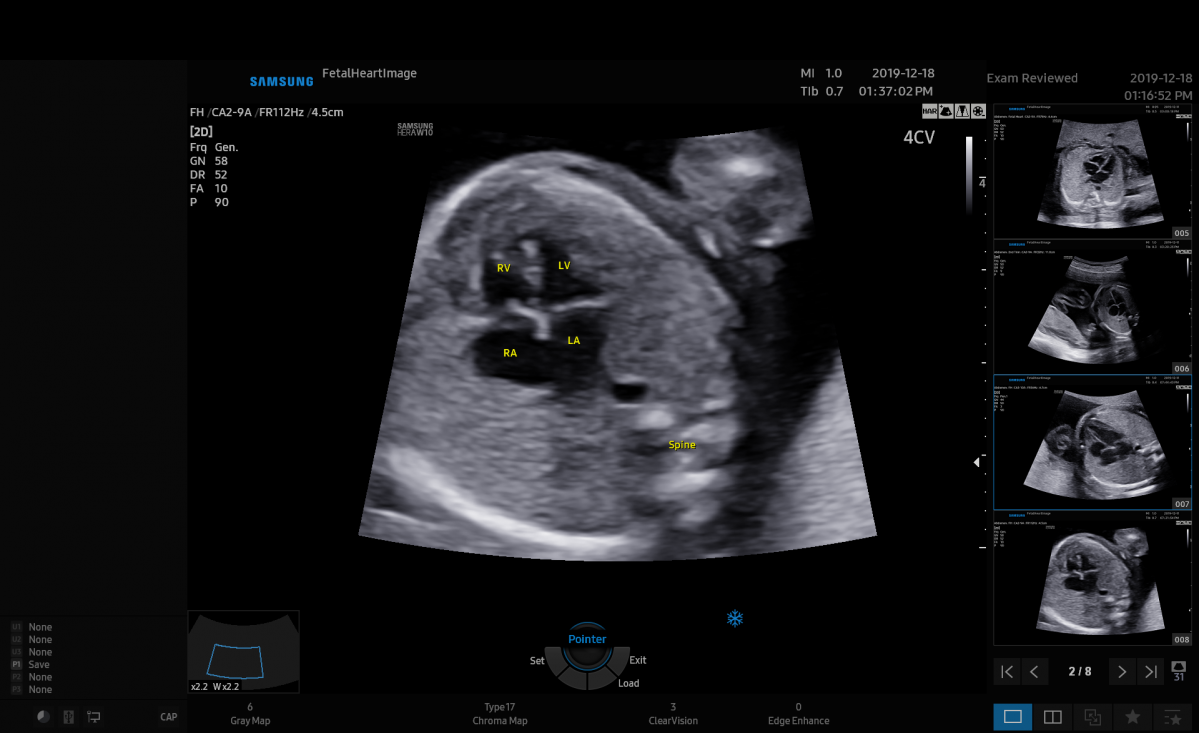

특히 하트어시스트는 선천성 심장 질환을 딥러닝 방식을 적용해 빠르고 정확하게 자동 측정한다.

올 6월 의료영상분석장치 소프트웨어 2등급을 획득해 삼성메디슨 최초 AI 의료기기로 허가받은 바 있다.